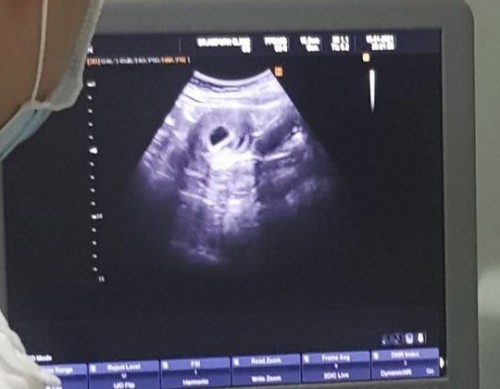

ขออนุญาตสอบถามนะคะ พอดีไปซาวน์มาเมื่อวาน เอามือถือถ่ายรูปไว้จากเครื่องซาวน์ พอกลับมาดูรู้สึกเหมือนเห็น2ถุง แต่คุณหมอไม่ได้พูดว่ามี2ถุงค่ะ อยากทราบว่าจะมีโอกาสเป็นแฝดมั้ยคะ

ถ้าแฝดหมอต้องแจ้งแล้วค่ะ เพราะแฝดเป็นการตั้งครรภ์ที่ไม่ปกติ เราเคยท้องแฝดถุง2ใบขนาดจะไล่ๆกันค่ะ